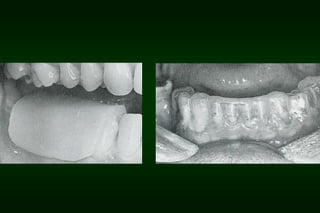

Types of Provisional Restoration II.Customized resin restorations 1. Direct technique b. Direct custom-carved (block-temporary)

Types of Provisional Restoration II.Customized resin restorations 1. Direct technique Disadvantages: • • • • Adverse pulpal or soft tissue reaction to monomer and increased temperature Allergic reaction Locking of restoration into undercuts Consuming chair time

Types of Provisional Restoration II.Customized resin restorations 1. Direct technique Avoiding potential problems • • • • Remove provisional restoration from teeth while in plastic stage Allow final polymerization to occur extraorally Use water coolant Use reline technique